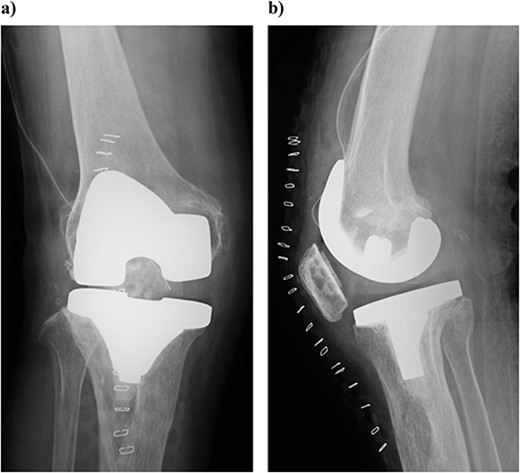

The knee was replaced with a Scorpio NRG PS type system (Stryker Orthopedics, Mahwah, New Jersey). The distal femur was cut with an intramedullary rod guided at 6° valgus. The tibia was cut with an extra medullary rod 10 mm from the medial joint surface, and a cutting guide was installed at a posterior inclination of 0°. The tibia was reamed, once a depth of about 30 mm was reached, the reamer could not be easily advanced. Once the tip of the reamer was confirmed, the tendon fiber was wrapped around the remar (Fig. 3). When palpated from the anterior lateral side of the tibia, the invasion of the patellar tendon into the bone marrow was confirmed. The patella was cut 8 mm from the articular surface. In addition, poor tracking of the patella caused lateral release. All of the prostheses were fixed using bone cement. Slight dilation of the medial joint space was observed at the time of closure, and the fascial was sutured with an overlapping stitch (Fig. 4). The operation time was 190 minutes and the amount of intraoperative bleeding was 238 ml.

Plain radiography immediately after the surgery: (a) front and (b) lateral side. A slight dilation of the medial joint space is observed.